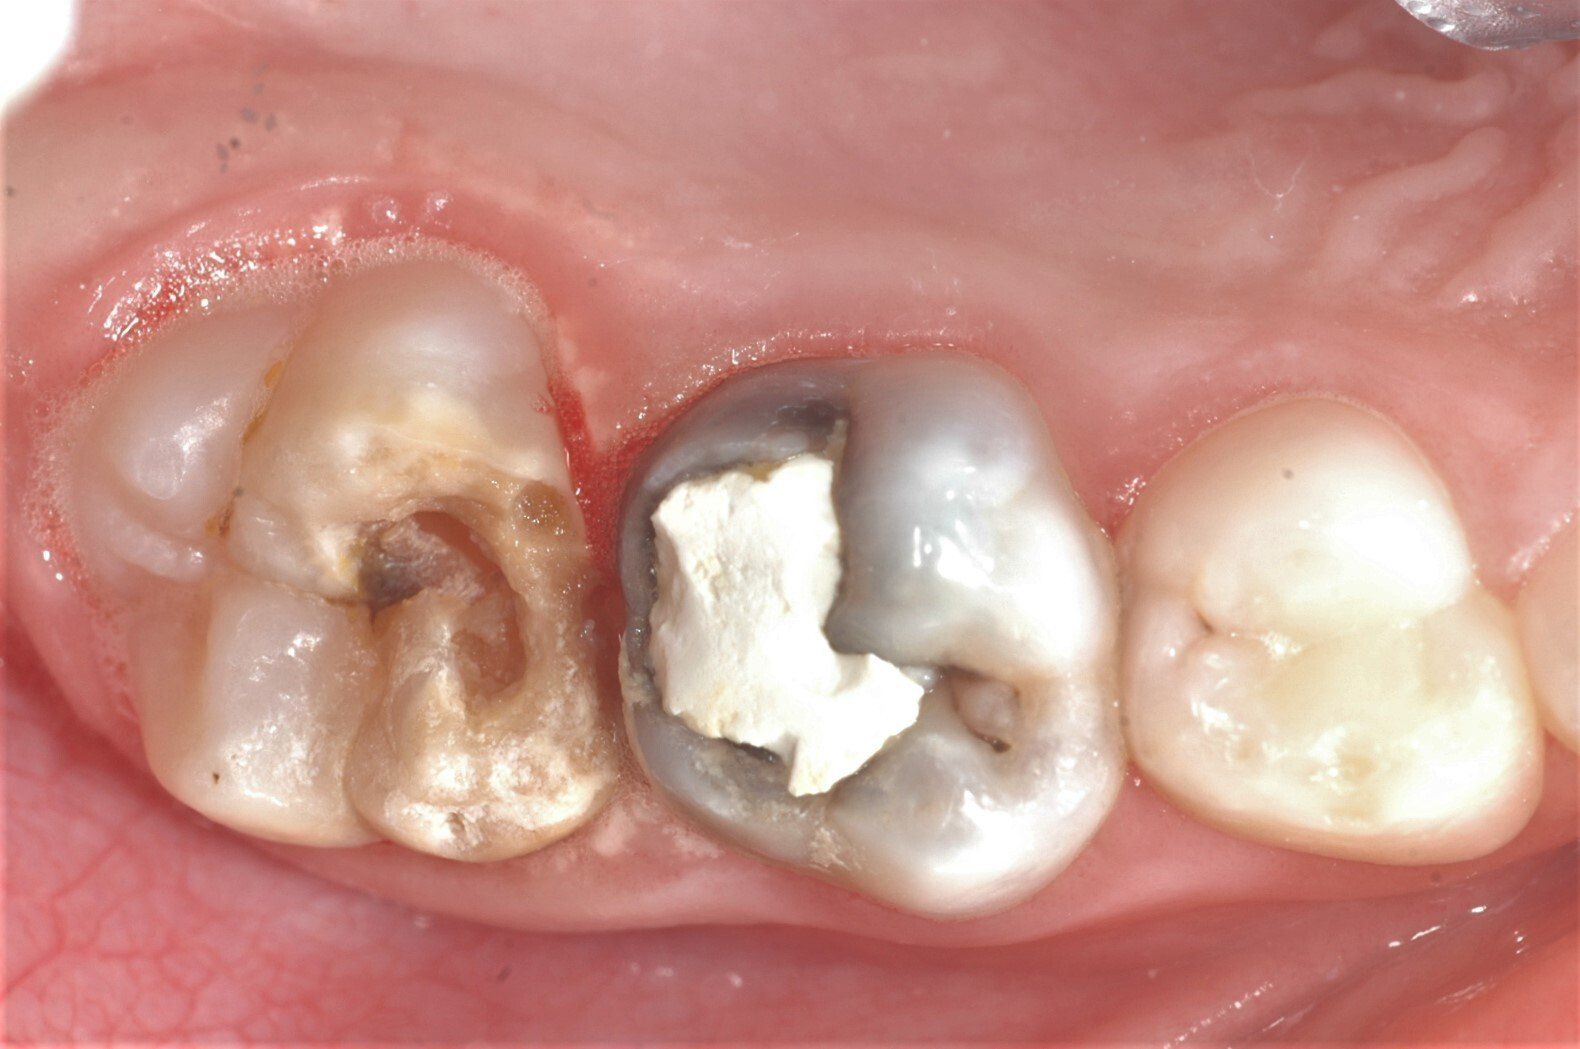

Etwa ein Fünftel aller Kinder in Deutschland sind betroffen. Die Zähne weisen scharf begrenzte, opakweiße, gelbe oder braune Verfärbungen auf. Sie sind weniger widerstandsfähig gegenüber Kaubelastung und kariesanfällig. Oft kommt es bereits kurz nach dem Durchbruch zu Abplatzungen und exzessiver Karies. Zähne mit MIH reagieren sehr empfindlich auf thermische Reize. Manchmal ist schon das tägliche Zähneputzen schmerzhaft und das Essen heißer oder kalter Speisen äußerst unangenehm.

Bei Substanzdefekten, Karies und starker Empfindlichkeit sind Compositefüllungen und eventuell stützende Edelstahlbänder die beste Versorgung. Hier ein Fall aus unserer Praxis: